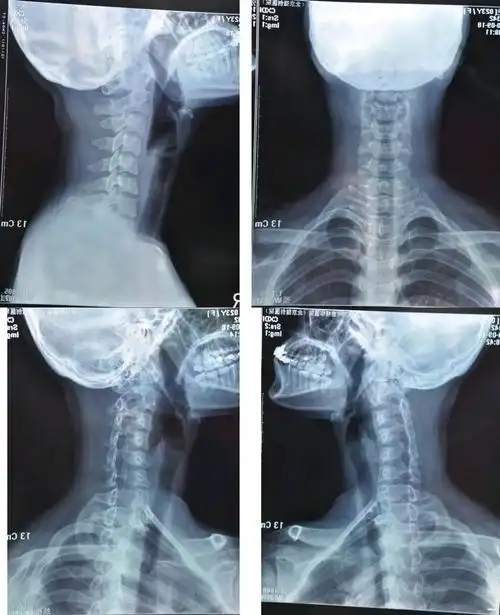

什么是颈椎反弓?

当颈椎反弓时,容易压迫颈椎周围的神经,引起神经症状和严重的后果.

颈椎反弓越来越常见严重还会引起瘫痪

颈椎反弓